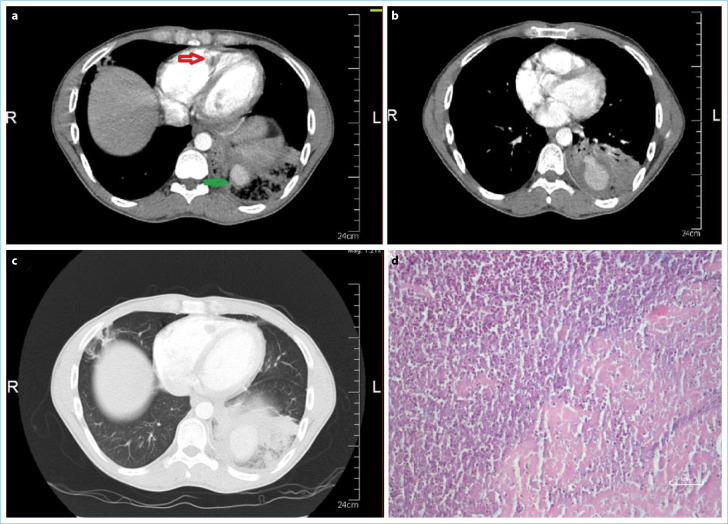

Behçet's Syndrome (BS) is a chronic vasculitis of unknown etiology. Arterial involvement occurring in the pulmonary artery is associated with poor prognosis. It may cause pulmonary thrombus (PTE) and aneurysm (PAA) which may also lead to a rare complication, intracardiac thrombus. PAA and PTE can be complications of BS and are associated with high morbidity and mortality. A 30-year-old male patient had a fever of 38.4°C, recurrent oral-genital ulcers, shortness of breath, cough, and sputum. In this case report, medical history, clinical and laboratory examinations, radiography, echocardiography, and computer tomography imaging examinations were performed. PAA, PTE, intracardiac and left popliteal vein thrombosis, and infective endocarditis were present. The patient was diagnosed with BS according to the International Study Group criteria. Surgery was performed for intracardiac thrombus. Vegetation within the thrombus was demonstrated histopathologically. The patient's clinical condition and laboratory tests improved with intervention and medical treatments. The patient with BS, PAA, PTE, intracardiac thrombus, and infective endocarditis was successfully treated with pulmonary embolization, antibiotics, and systemic immunosuppression, despite its rarity, poor prognosis, and high morbidity and mortality rates.

Abstract Image